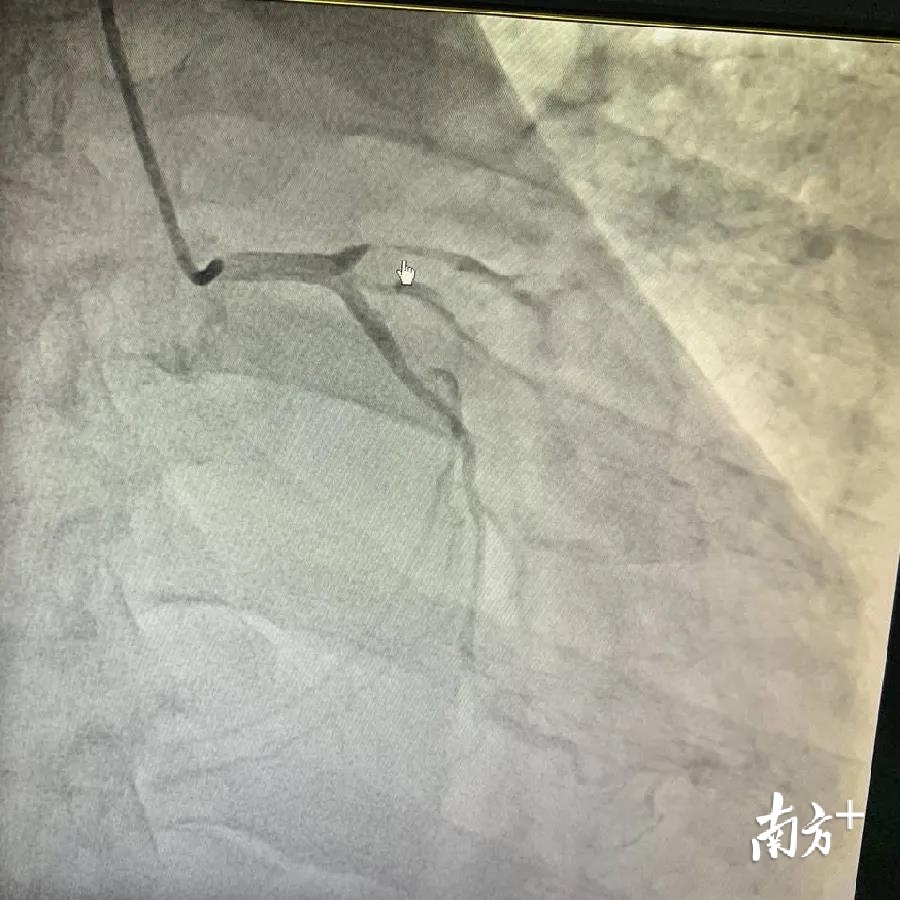

为了更加准确判断钱先生的病情,兰军为钱先生进行抗心衰治疗后,为患者行冠状动脉造影术。当他看到钱先生的心脏血管的情况时,兰军脸色变得十分严峻:造影术显示左前降支近段完全闭塞;回旋支远端重度狭窄,右冠状动脉中段慢性完全闭塞。

兰军马上召开紧急病情讨论,由于钱先生的情况危殆,血管堵塞情况严重,为降低手术的风险,兰军最后决定通过两次手术分别打通堵塞的血管。在确认手术方案后,兰军向急性闭塞的“左边的血管”植入1枚支架,在完成支架手术后,钱先生心绞痛的感觉消失。